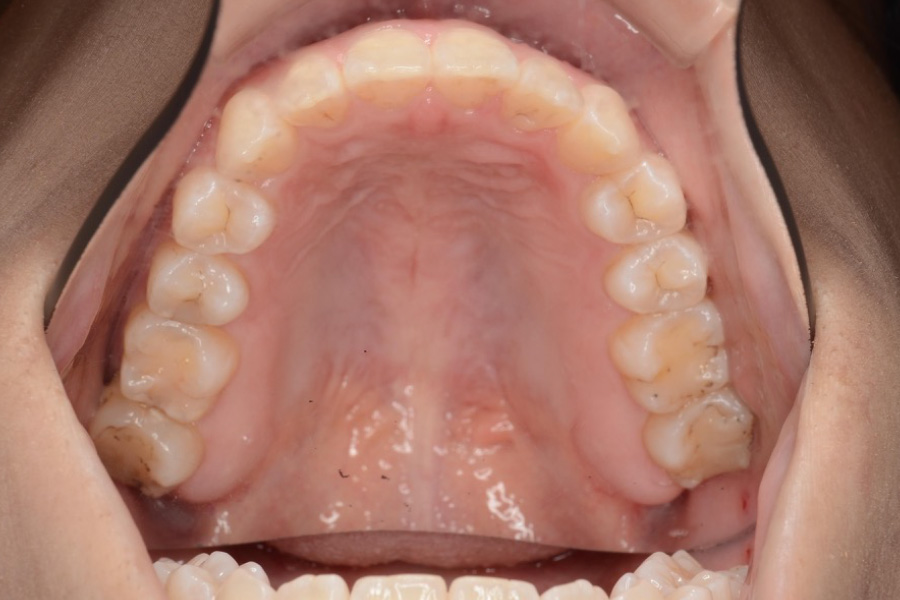

治療前

主訴 歯のガタつき

治療内容 インビザライン矯正

非抜歯